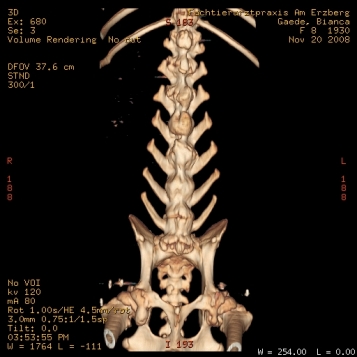

Bezüglich des CT, da ist einfach der große Vorteil, dass man auch Probleme der Knochen sehen kann, die eventuell zu klein sind oder nicht genau genug auf dem Röntgenbild.

Mal als Vergleich